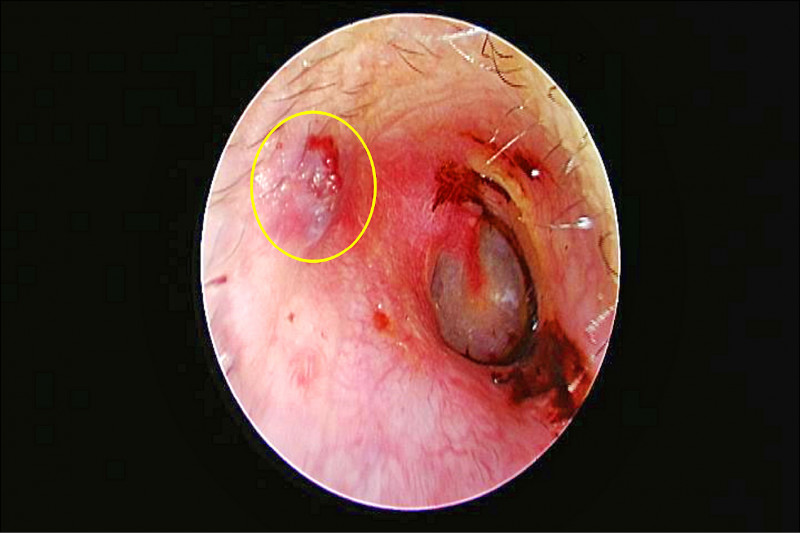

一位50多歲的女性指著自己的右耳說:「我的右耳好痛,已經有3天了,有吃過止痛藥,但是依然在痛……」拿起耳鏡再仔細一瞧,在右側外耳道內看到一個白斑的圓形物體,內側靠近耳膜處還有些小黑點(圖1)。此刻我的心中已悄然浮現「昆蟲叮咬」的臆斷。

待向病患說明外耳道可能有昆蟲,疼痛的來源應是蟲子叮咬外耳道皮膚所致,藉由開刀房內視鏡的放大影像,配合必要的鑷鉗、夾子等,顯然手術室會是比較合適的場合來移除這個不速之客。隨後從內視鏡放大的影像可以發現這是一隻蜱蟲(tick)的口器已刺入耳道皮膚(圖2),圓圓的身軀應是已吸了不少的血。經由咬合鑷鉗等內視鏡器械,將此蜱蟲夾除。術後傷口恢復良好,耳部疼痛也戲劇性地快速消除。

由於蜱蟲在叮咬時會分泌具有麻醉及抗凝血的物質,因此在叮咬時大多無明顯症狀,但叮咬的傷口造成局部充血、腫脹、急性發炎反應(圖3),還可能引起後續感染。